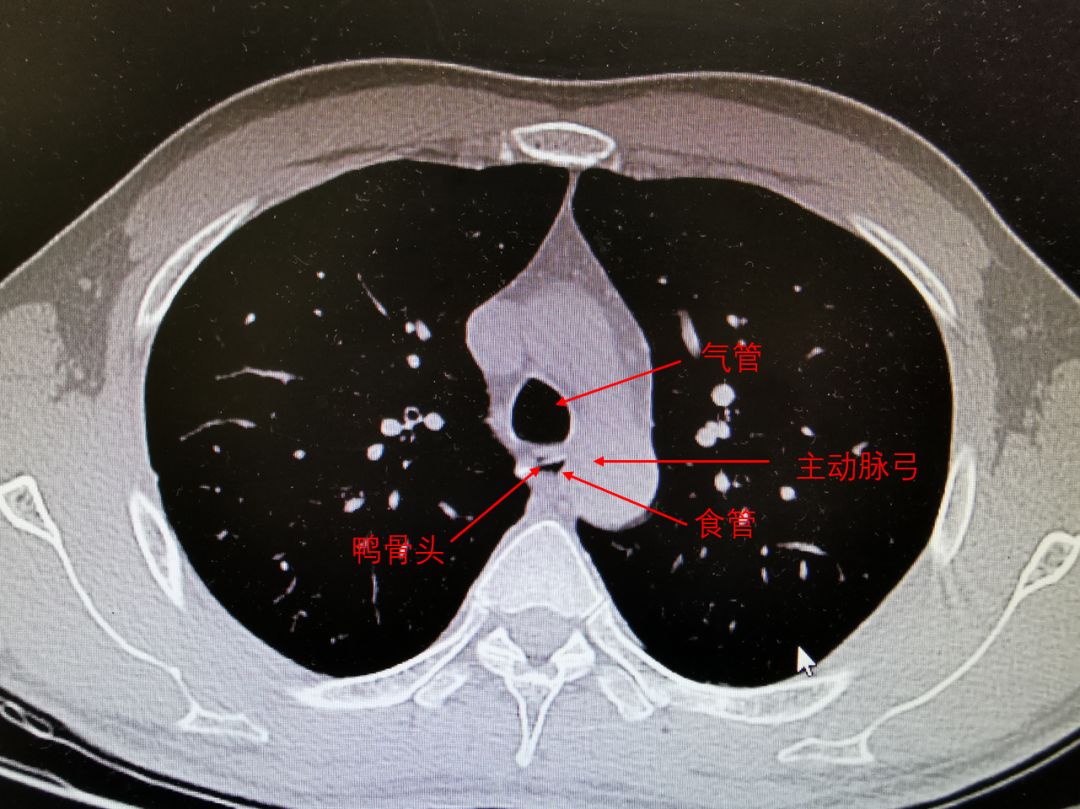

我的胸部CT(带注解)

站在一旁的消化科协理眉头紧蹙,“啧,你这个有点复杂,很靠近主动脉,而且有点穿透了,非常危险啊。”

我又看了一眼,我的鸭骨头离主动脉弓只有一墙之隔,大概只有3毫米,一旦穿破主动脉,引起大出血,那我就凉了。